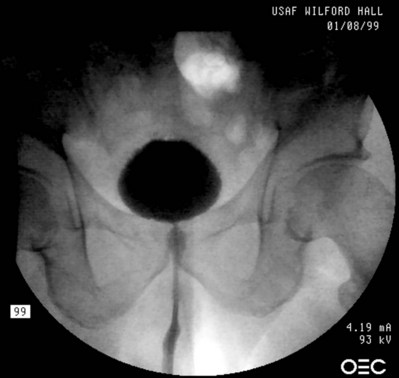

More recently, Cespedes and associates (1996) described McGuire’s modification (limited lateral vaginal dissections) of the Ingelman-Sundberg procedure in 25 women with urinary urgency incontinence and detrusor overactivity who had failed behavioral and medical therapy (Fig. 75–1). Transvaginal local anesthesia was used as a test to determine which patients would benefit from the procedure, with significant improvement of urgency symptoms considered a positive test. Twenty-five patients were found to have a positive test; the number of patients unsuccessfully tested was not reported. Sixteen (64%) of these patients were cured of urgency incontinence at a mean follow-up of 14.8 months. Of the 16 patients cured, 9 patients required one medication, and 2 required two medications. Madersbacher (2000) comments that a follow-up period of 15 months is too short to determine long-term effects.

Figure 75–1 Terminal pelvic nerve branches enter the bladder near the trigone. A, To assess preoperatively in clinic whether the patient would benefit from the procedure, local anesthetic (0.25% bupivacaine) is injected subtrigonally to block the nerves which would be denervated by the operative procedure. B, Normal saline is injected submucosally to facilitate dissection of the vaginal mucosa off the bladder. C, Position of the trigone outlined by a catheter balloon inflated to 30 mL. D, Inverted-”U” vaginal incision is made. E, Dissection of the vaginal mucosa and deeper tissues off the underlying bladder. F, Completed dissection.